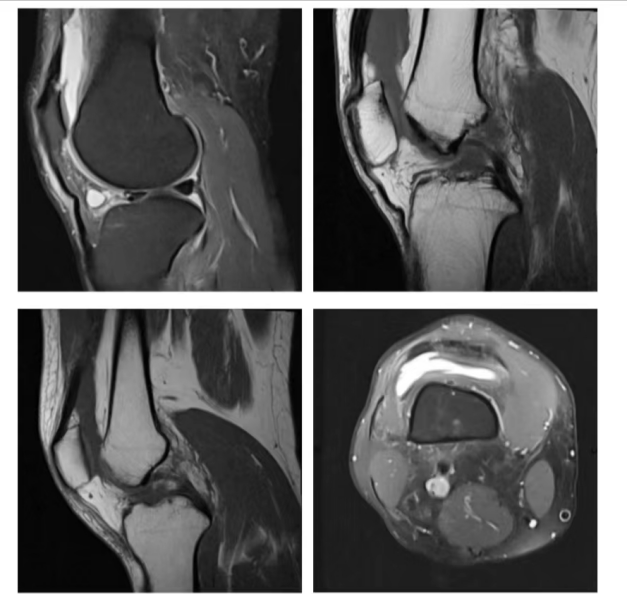

关节成像

软组织分辨率较CT更高